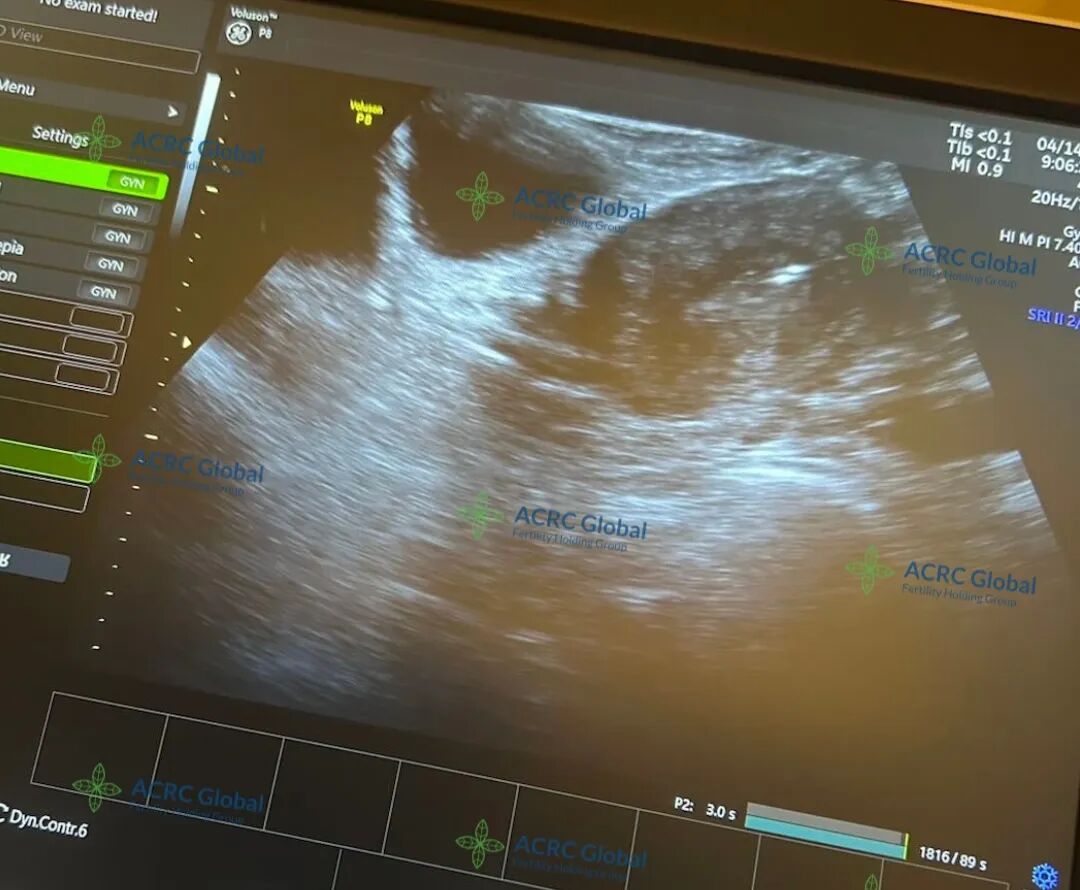

自移植以来,爱妈一直非常配合,不仅定期更新近况,还主动分享每次产检照片,让准妈妈远在国内也能放心。用药、打疫苗、日常调养,她都认真对待,事事细心,沟通顺畅,让整个孕期进展得非常顺利。大家都满怀期待,希望这个小生命能在她的温柔守护下,健康成长,顺利到来!